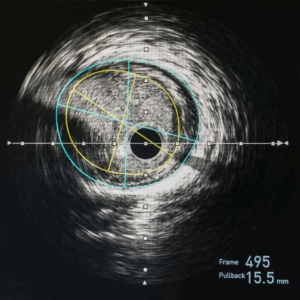

Cleerly Health CCTA Expedited

Cardiac Testing

$1,800.00(+Processing Fee)